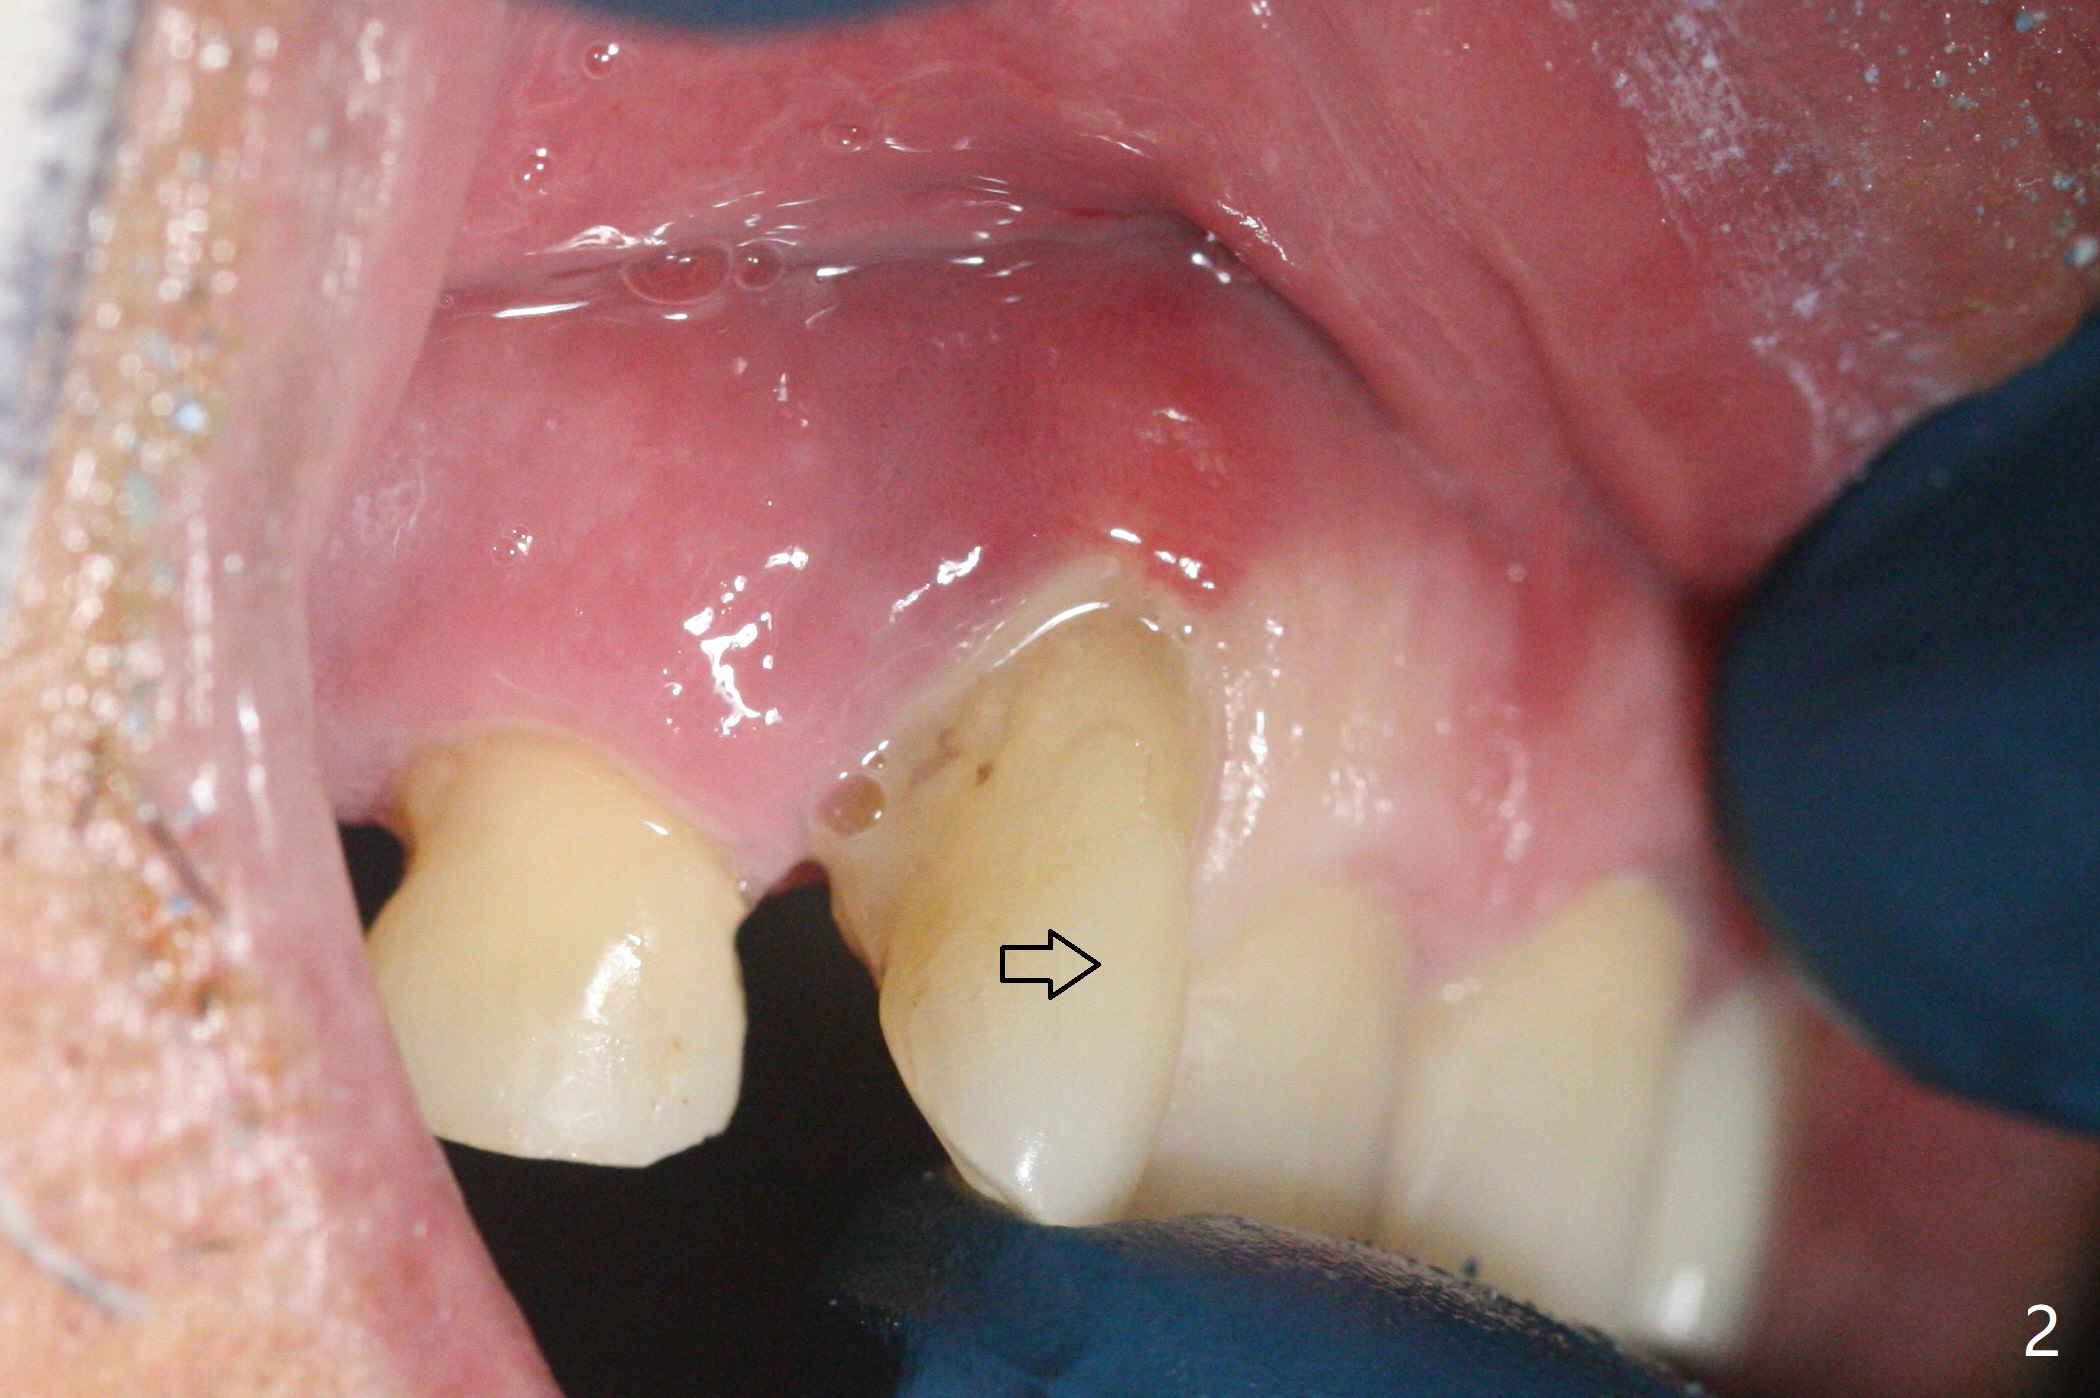

68岁男士右上2严重骨质吸收,颊侧骨板缺失,术前牙龈退缩也十分明显(图一,二),术中对脆弱牙龈缘(图三:*)不应施加任何压力或者牵拉,更不能切开,保持最佳血供。按照术前设计,在牙槽窝腭侧钻洞(图四),植入2.5x15毫米一段式植体(扭力>35Ncm),基台特长(牙龈厚,图五)),基台位于合适修复位置(图六),4-5毫米螺纹颊侧暴露(图七:*)。植骨(图八(CT冠状切面(拔牙后:黑色)):箭头)前,将PRF膜(白线)一头(a)插入牙槽窝颊侧,另外一头(图八,九:b)放置颊侧牙龈颊侧。然后填入粘性骨粉(图九:S;图十四:*),将b头PRF膜往下翻,它末端事先冲一个洞(punch a hole using sterilized rubber dam punch),插入基台(图十(粉红色),十一),这样PRF膜不移位,牢靠地固定骨粉(图十(红圆圈),图十四:*),最后使用树脂敷料覆盖伤口(图十二,十三:A),同样需要基台(箭头,也就是一段式植体)固定,也就是没有即刻植体,就没有骨粉固位。术后两个月伤口缩小,肉芽组织生长(图十五)。撤除树脂敷料后,制作临时牙冠,半个月后唇侧植体有些暴露(图十六),嘱咐强化口腔卫生。